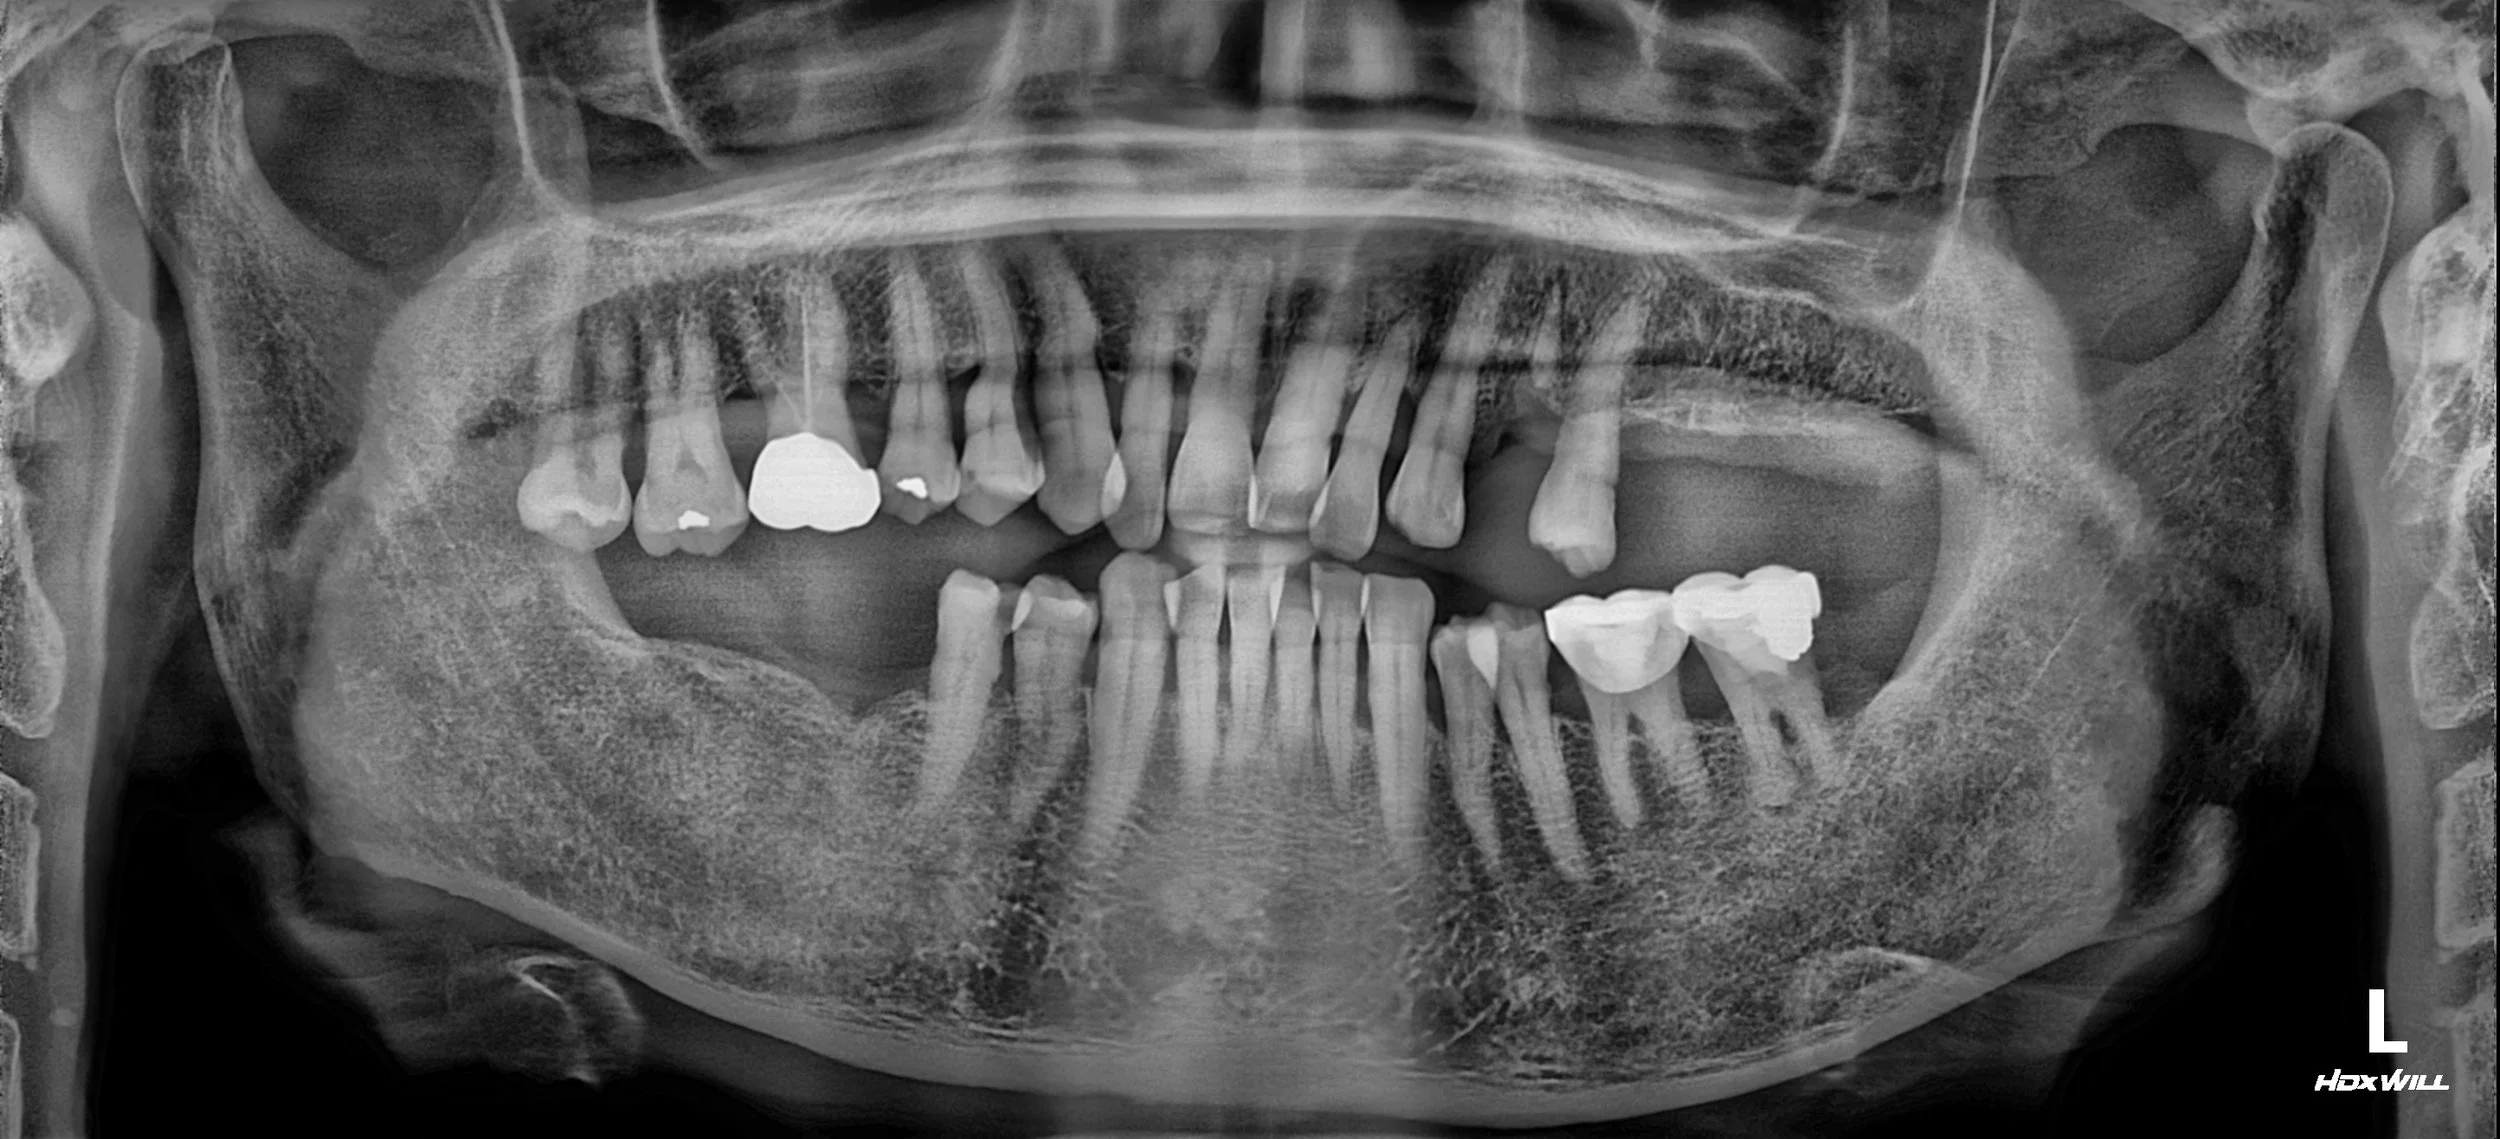

OPG - BEFORE